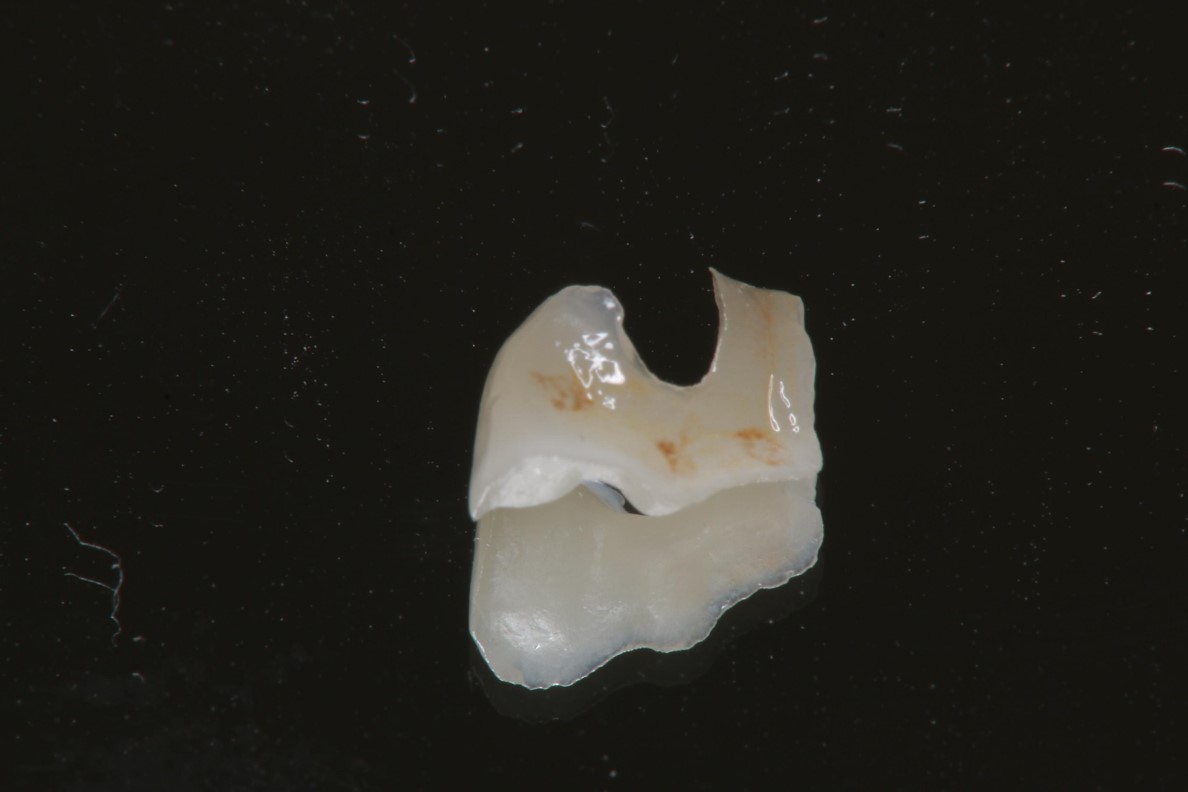

大臼齒的陶瓷崁體